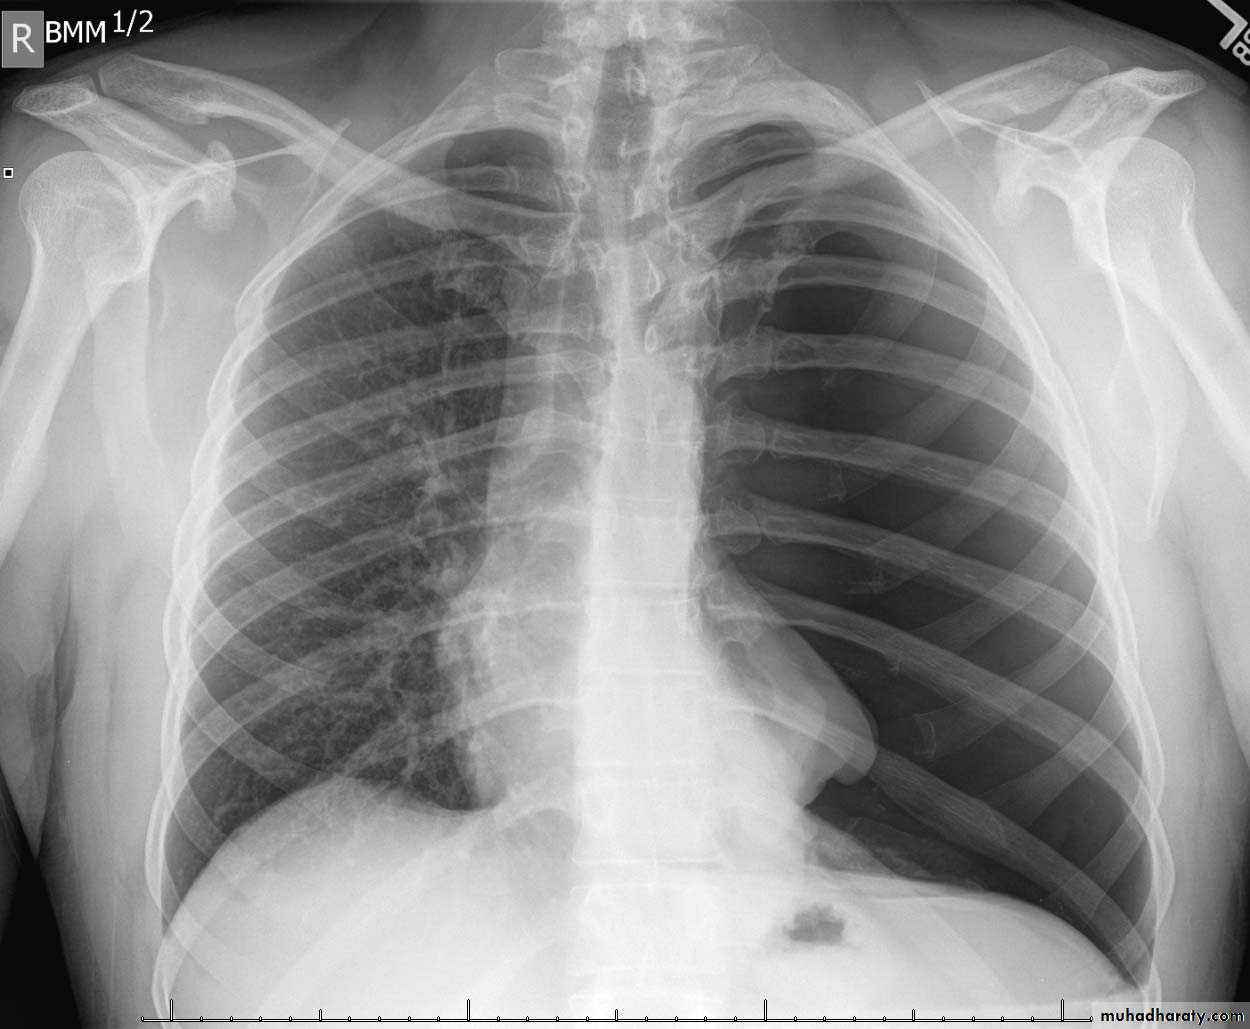

Radiolucent area devoid of lung markings in the upper left lung

Visible viseral pleural edge as very thin sharp white lineRadiolucent area devoid of lung markings in the upper left lung

Visible viseral pleural edge as very thin sharp white linePneumothorax

Radiolucent area devoid of lung markings in the periphry of the right lung with visible viseral pleural edge